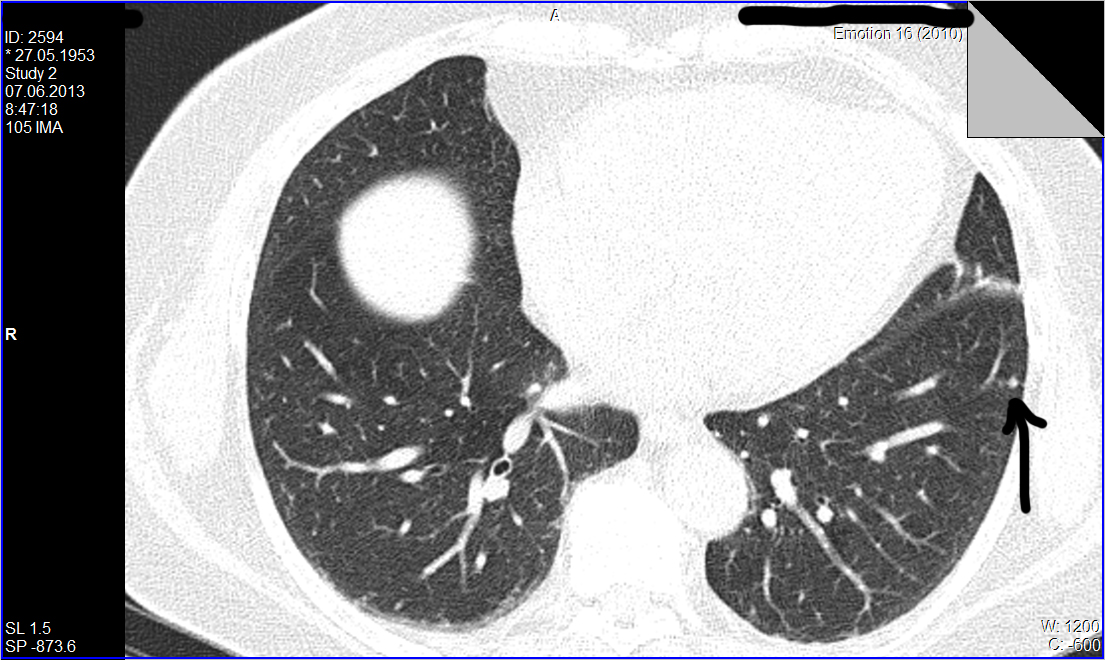

Уважаемые колеги, нужен совет более опытных чем я КТшников. А вопрос такой: как трактовать находки в виде одиночных мелких очагов в легких при относительно спокойном анамнезе.

Для примера приведу такой случай: из туб. диспансера направлена женщина после туб контакта, пожелавшая сделать кт легких. Жалоб нет, проведеные анализы без особеностей. Просмотрев томограммы я нашел только два единичных очага в базальных отделах левого легкого. Какая у вас тактика действий по поводу таких находок?